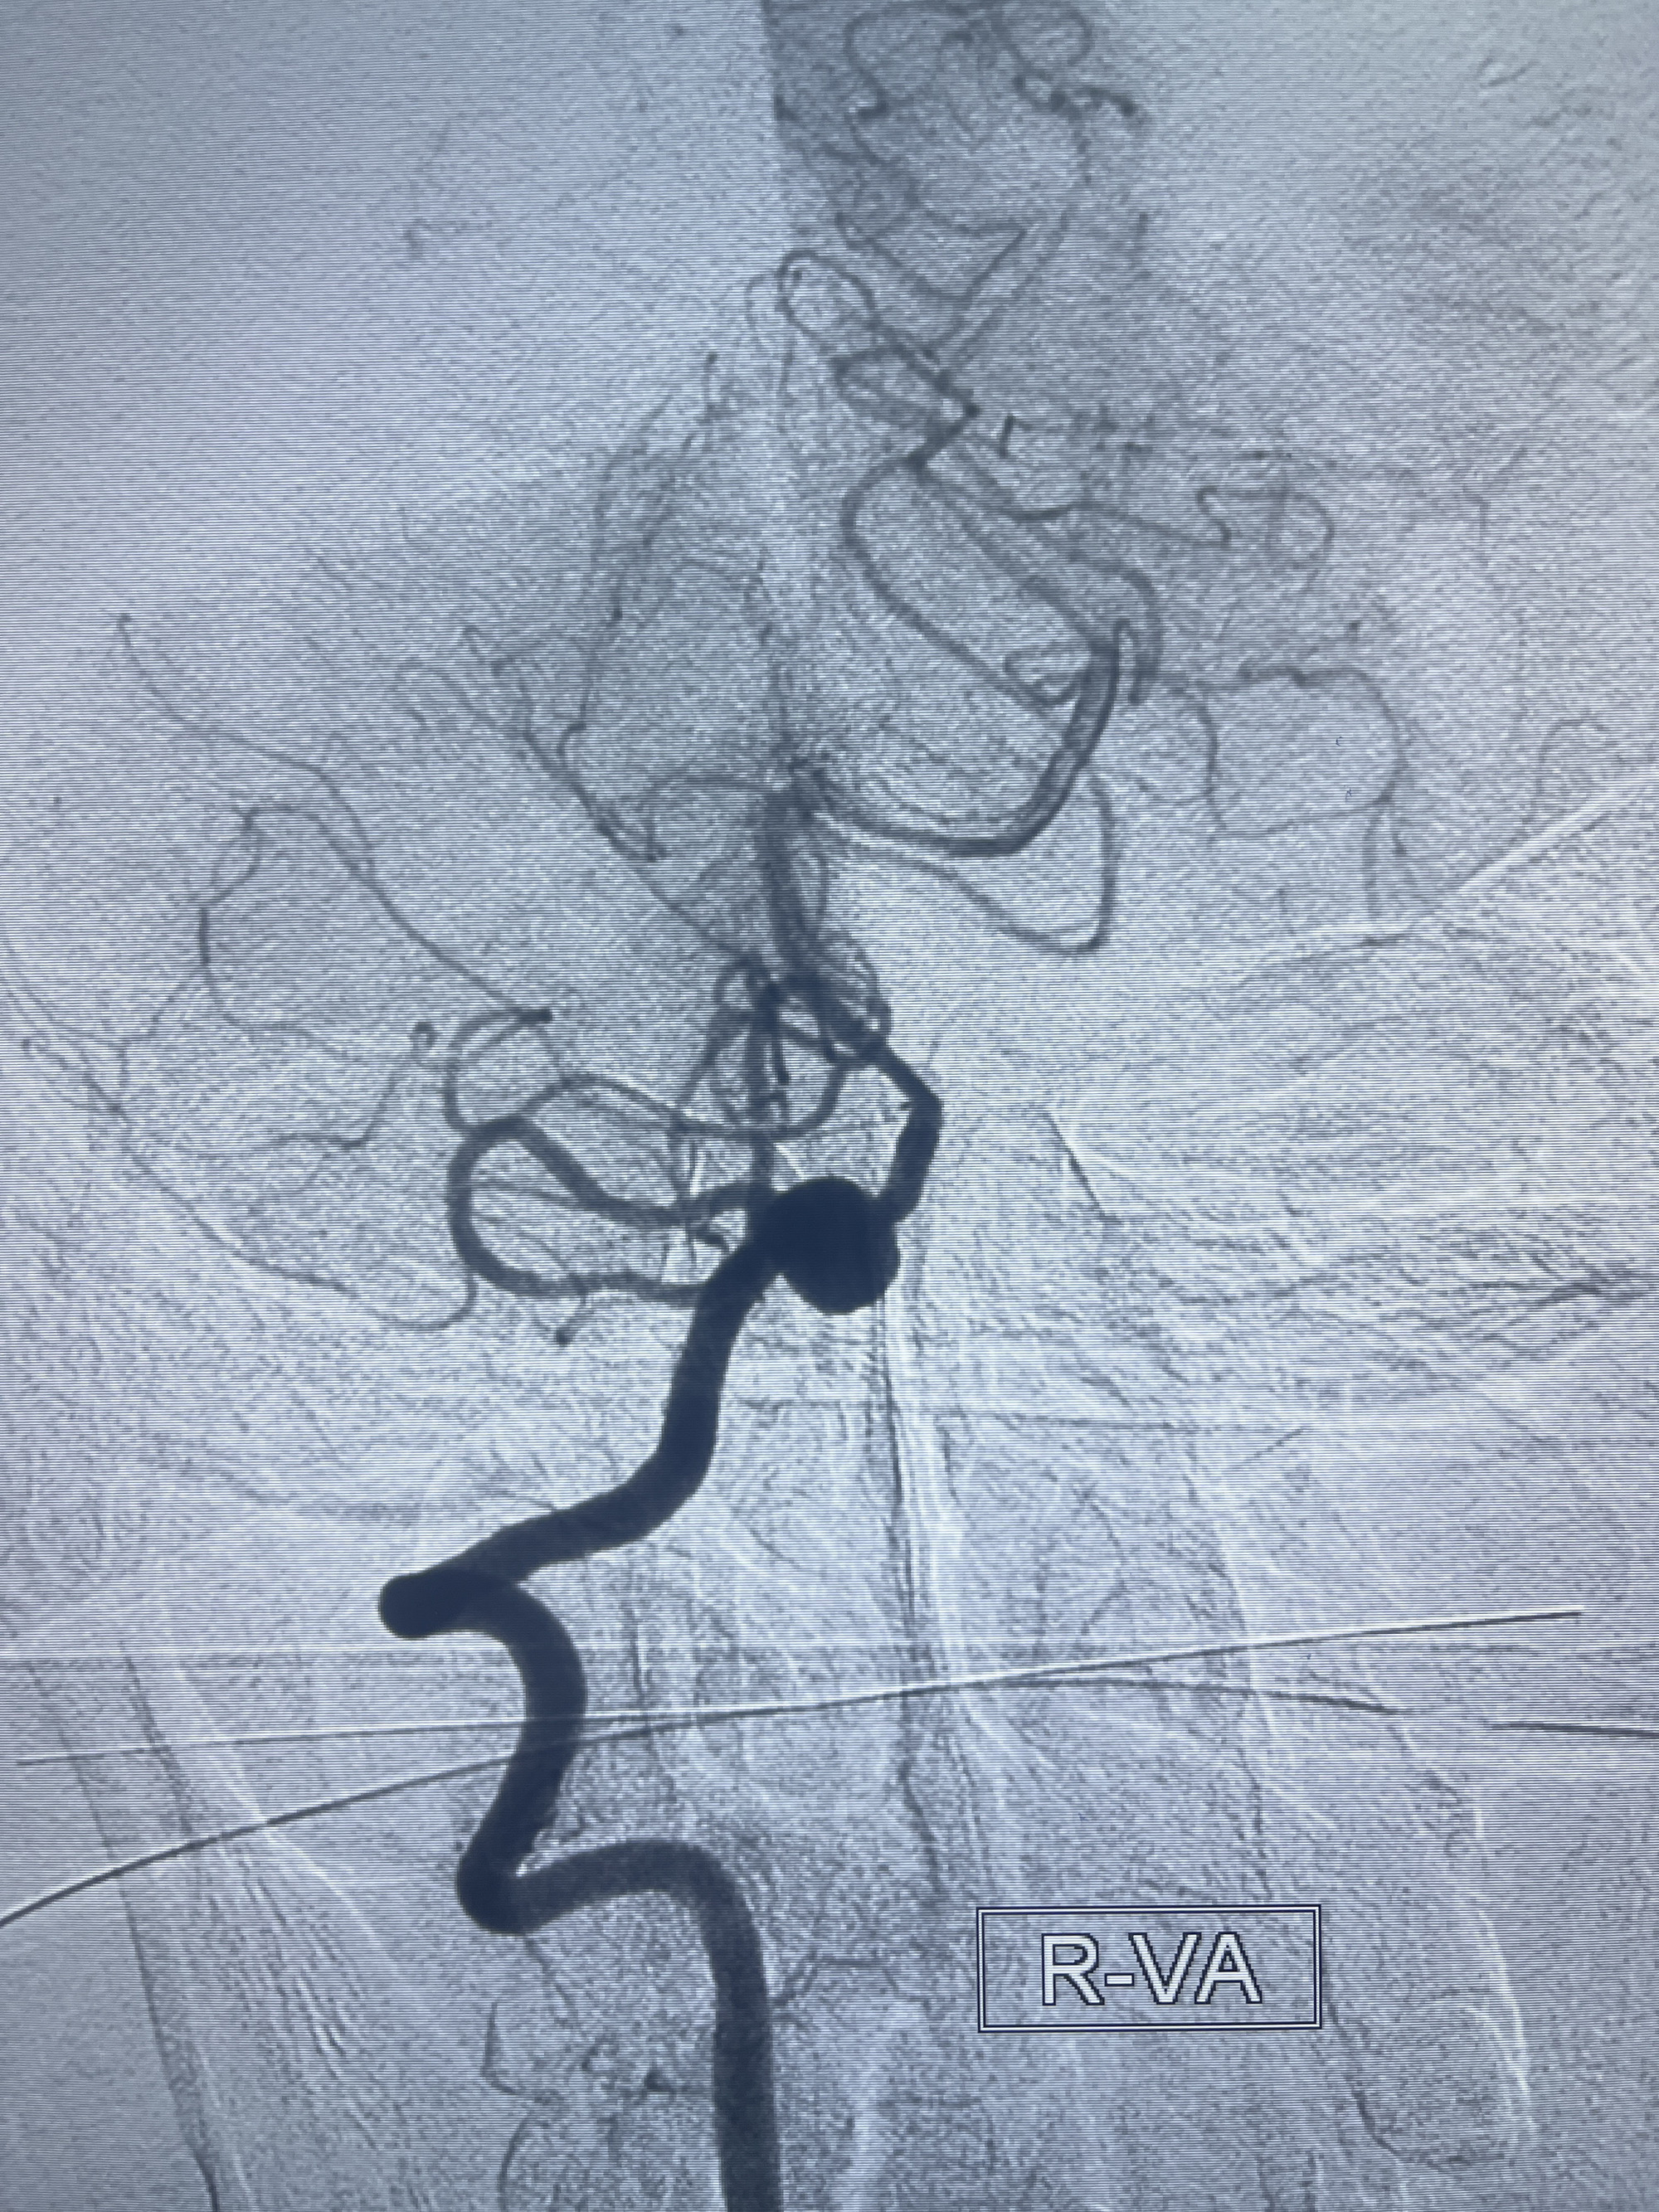

202.04.28脑血管造影:右侧大脑后动脉远段闭塞,右侧椎动脉V4段可见“囊状造影剂填充影”,大小7.64*7.65mm,可见PICA由动脉瘤发出;